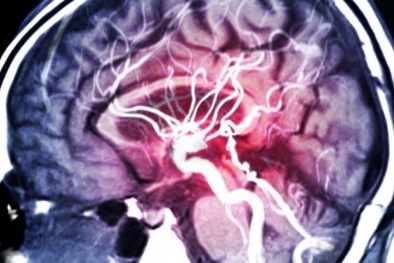

Sự ra đời của hệ thống AI với khả năng dự đoán động kinh gần như hoàn hảo

(VietQ.vn) - Chúng ta đã thấy được chiếc vòng đeo tay thông minh có thể dự đoán các cơn động kinh hàng đêm, nhưng mới đây, hai nhà nghiên cứu là Hisham Daoud và Magdy Bayoumi của Đại học Louisiana tại Lafayette, đã tạo ra thiết bị thậm chí còn hứa hẹn hơn: một hệ thống AI có thể dự đoán các cơn động kinh với độ chính xác 99,6%. Ngoài ra, hệ thống này còn có thể đưa ra tín hiệu cảnh báo trước 1 giờ đồng hồ.